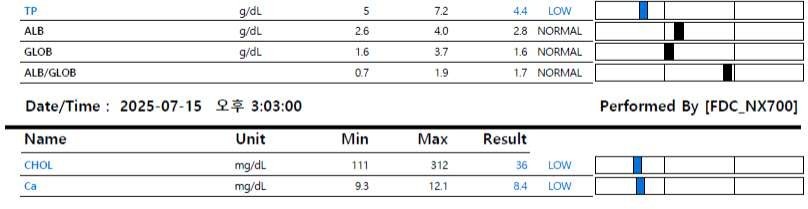

- 혈액 속 단백질 수치가 낮아진 상태(저알부민혈증)

병원 내 기본 검사 결과, 체중은 4.7kg이었고 체온은 38.4℃로 비교적 안정적이었으나, 심박수와 혈압은 다소 높은 편이었습니다. 만성 장 질환의 중증도를 평가하는 지표인 CCECAI 점수는 13점으로, 중등도 이상의 만성 장 질환이 의심되는 상태였습니다.

또한 소변 단백/크레아티닌 비율(UAC)은 12.7로 확인되었고, 흉수의 성상은 염증이나 감염보다는 단백질 부족으로 인해 발생한 형태(transudate)로 판단되었습니다.

이상의 검사 결과를 종합하여, 나무는 단백 소실성 장질환(Protein-losing enteropathy, PLE)이 가장 강하게 의심되는 상태로 평가되었습니다.

PLE(단백 소실성 장질환) 이란, 장 점막이 손상되면서 혈액 속 단백질(특히 알부민)이 장을 통해 빠져나가는 상태를 의미합니다.

PLE가 발생하면 저알부민혈증, 복수, 흉수, 체중 감소, 전신 부종과 같은 증상이 나타날 수 있으며, 단순한 약물 치료만으로는 조절이 쉽지 않은 경우가 많습니다.

또한 PLE(단백 소실성 장질환) 관리에 있어서는 혈액검사 수치, 특히 알부민 수치에만 지나치게 집중하기보다는 아이의 체중 변화, 전반적인 컨디션, 식욕과 임상 증상을 함께 종합적으로 평가하는 것이 중요합니다.